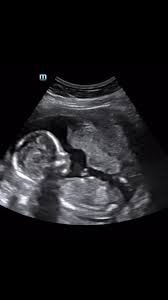

Las imágenes, capturadas con tecnología avanzada, ofrecen una visión única y detallada del entorno en el que crece un bebé antes de nacer. Se puede observar al diminuto ser humano moviéndose, succionando su dedo y explorando su entorno acuático.